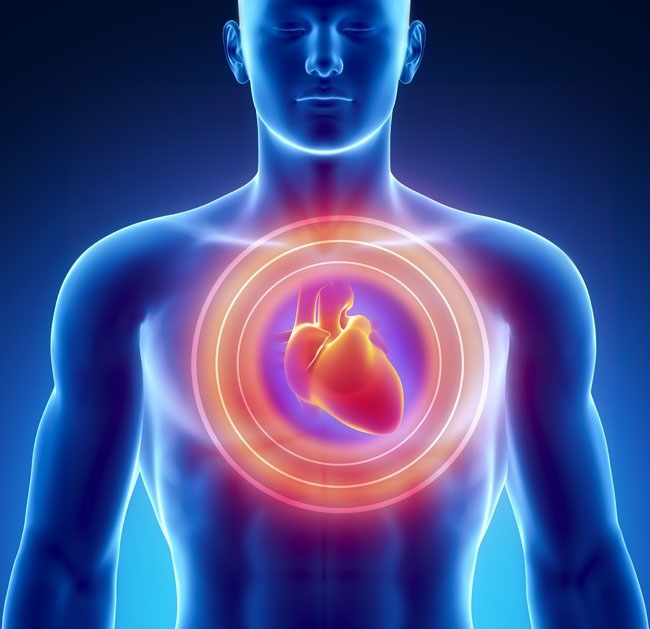

8 dấu hiệu dự báo cơn đau tim trước khoảng 1 tháng

Những thay đổi bất thường dù là nhỏ nhất dưới đây cũng có thể là dấu hiệu cảnh báo cơn đau tim. Tuyệt đối không nên thờ ơ vì chính sức khỏe của mình.

6. Nhịp tim không đều

Nhịp tim không đều thường xuất hiện khi hoảng loạn, lo lắng, đặc biệt là ở phụ nữ. Nó có thể xuất hiện bất ngờ theo 1 trong 2 trạng thái: loạn nhịp (nhịp tim bất thường) hoặc nhịp tim nhanh (tăng nhịp tim). Tập thể dục có thể kích thích sự gia tăng nhịp tim, đặc biệt là trong trường hợp mắc bệnh xơ vữa động mạch.

Mô tả: Nhịp tim bất thường kéo dài trong khoảng 1-2 phút. Nếu đồng thời cảm thấy chóng mặt và mệt mỏi quá mức hãy gọi ngay cho bác sỹ.

8. Đau tức ngực

Nam giới và nữ giới trải qua cơn đau, tức ngực với cường độ khác nhau. Triệu chứng này đặc biệt rõ rệt ở nam giới, khả năng xảy ra ở phụ nữ chỉ khoảng 30%.

Mô tả: Đau ngực có thể mở rộng cảm giác không thoải mái ở cả 2 bên cánh tay (thường là bên trái), hàm dưới, cổ, vai hoặc dạ dày.